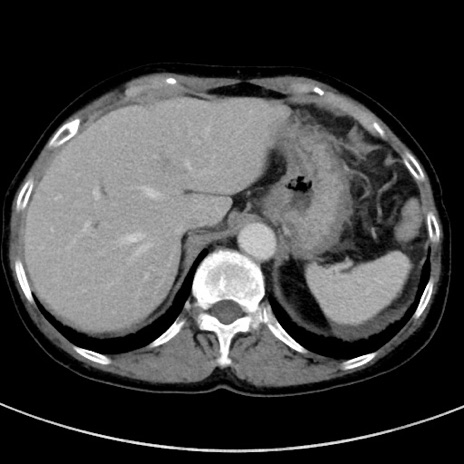

冠状断像

【症例】70歳代女性

【主訴】下腹部痛・嘔吐

【現病歴】2日前より腹痛あり。昨日嘔吐あり。症状改善しないため来院。

【既往歴】胃GISTに対して胃部分切除後。

【身体所見】BT 37.1℃、BP 128/77mmHg、腹部:平坦・軟、下腹部に圧痛あり。

【データ】WBC 10200、CRP 0.31